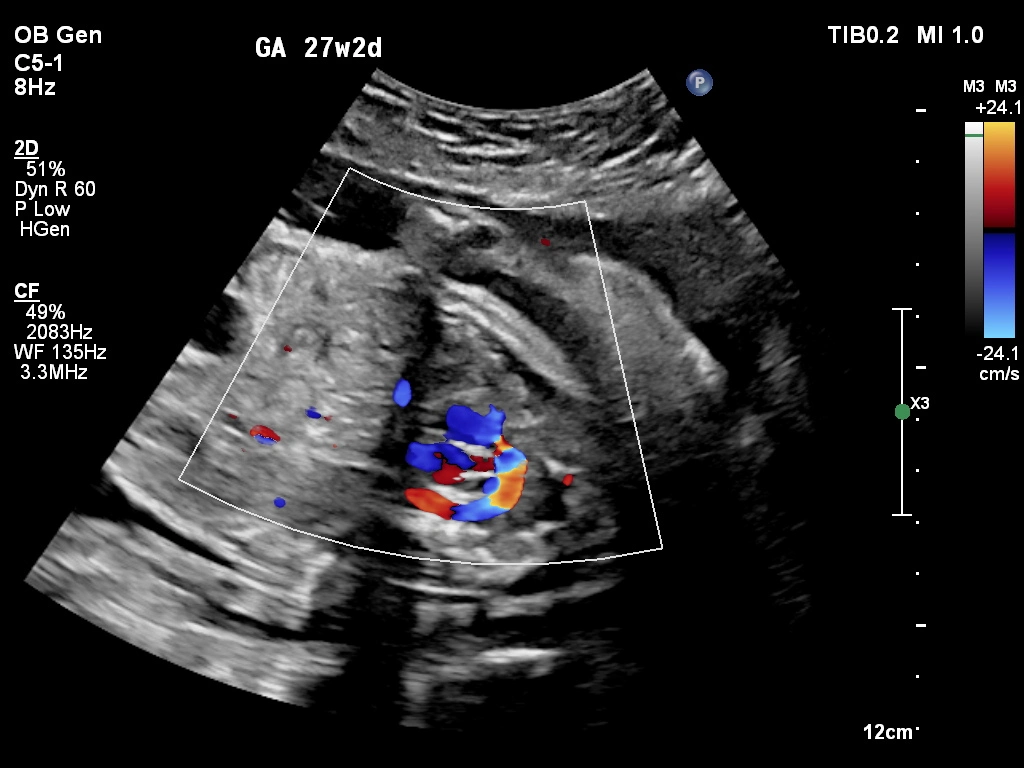

🔹 Fetal Echo / Adult Echo (Echocardiography)

Echo (Echocardiography) is a specialized ultrasound used to examine the heart. Fetal Echo evaluates the baby’s heart structure and function during pregnancy, while Adult Echo checks heart health in adults. It helps detect congenital heart defects, valve problems, and blood flow issues. If you need a fetal echo in Kathmandu, this test plays a vital role in early diagnosis and treatment planning.